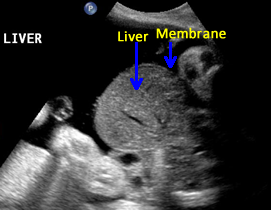

Above. Pentalogy of Cantrell. Case 1. 34 6/7 weeks gestation. Pentalogy of Cantrell showing associated omphalocele containing fetal liver. Note the thin membrane covering of the omphalocele defect.